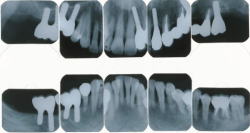

| Case1. Implant treatment to severe periodontitis; losing some tooth | |||||||||||||||||||||||||||||||||

|

| |||||||||||||||||||||||||||||||||